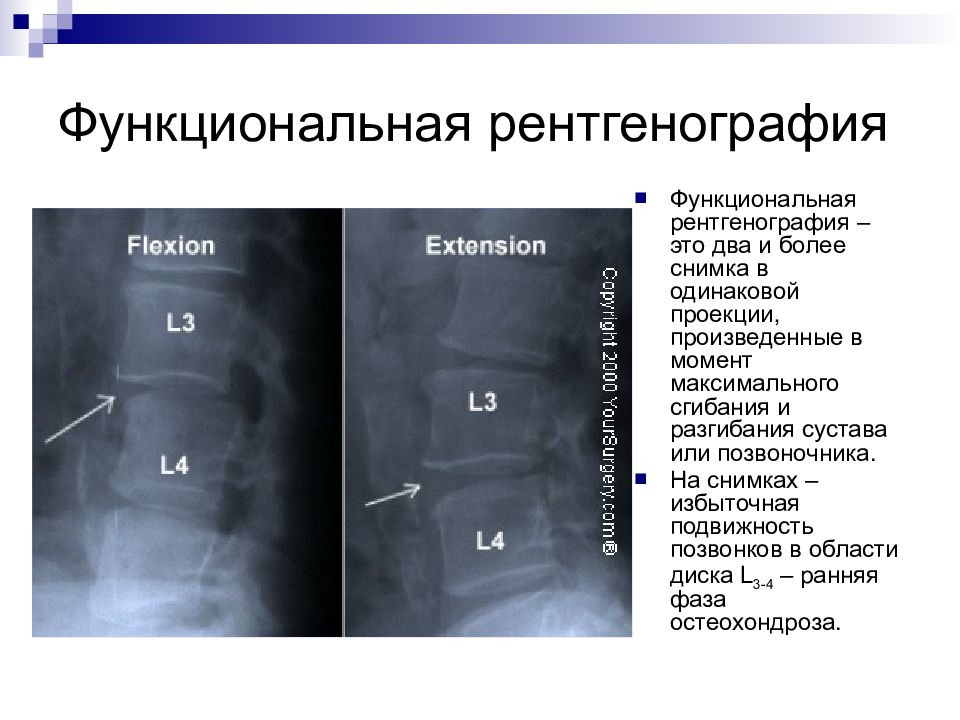

Мрт картина дегенеративно дистрофических изменений пояснично крестцового отдела позвоночника